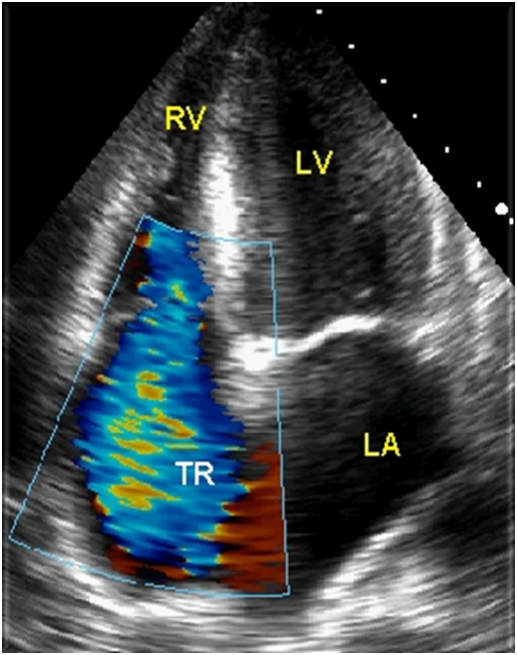

Tricuspid Regurgitation Color Jet

Assess TR jet width and length in all views. Adjust color gain, scale, and color box

Views in RVIT, SAX AO, A4C